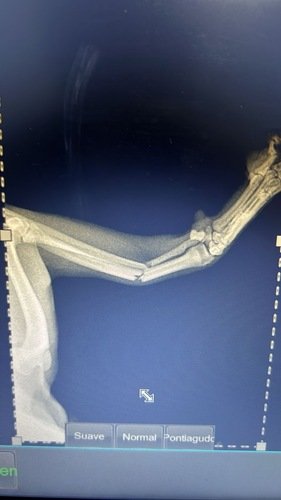

Oi, meu nome é Paçoca, não tenho 1 ano ainda e sou muito arteiro. Ontem quis fugir de dentro de casa pulando a janela, o que resultou na minha patinha quebrada, estou internado e preciso de cirurgia mas minha família não tem condições de pagar pois os custos são muito altos, por isso estou criando essa vakinha, se quiser ajudar, qualquer valor será bem vindo e ficarei muito grato. Estamos lhe encaminhando o orçamento solicitado:

👉🏽Consulta de Plantão:*R$ 220,00*👉🏽 Raio X:*R$ 220,00*👉🏽 Aluguel de bloco:*R$ 400,00*👉🏽 Internação:*R$ 60,00* x 4 = R$ 240,00👉🏽 Medicações pós procedimento: *R$ 70,00* x 4 = R$ 280,00👉🏽 Tratamento e medicações pós procedimento:*Á confirmar*